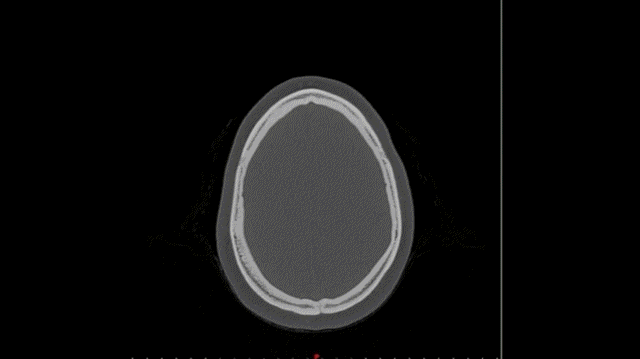

The short answer is that it’s exactly what it sounds like — it’s one specific medical procedure that’s designed for one specific patient. Patient-specific surgical approaches may include surgical cutting guides and/or manufactured implants, and they fit the patient and the procedure perfectly because they are designed based on CT or MRI scans of the patient. In short, everything about a patient-specific procedure is 100% customized to the patient’s anatomy, including patient-specific anatomic models, cutting guides, guides for the placement of bones and plates, pins, and implants that address and restore a patient’s bony anatomy.